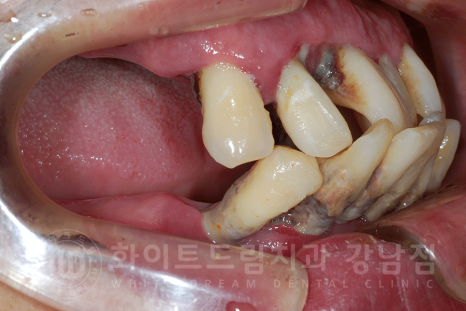

환자분의 남아있던 치아들을 모두 발치한 사진입니다.

치아 뿌리 주변에 거뭇거뭇하게 치석들이 굉장히 많이 있는 것이 보이시나요?

이렇게 치아 부분까지, 잇몸 안쪽에 위치해있는 치석을 '치은연하치석'이라고 합니다.

치주염을 유발하는 주된 원인들이죠.